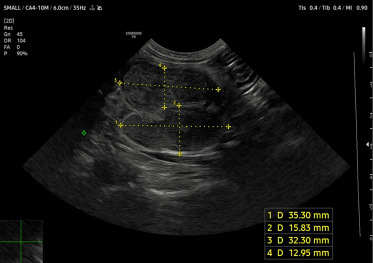

Obraz radiologiczny pozwala jedynie podejrzewać FGESF, nie jest jednak wystarczający do rozpoznania. W badaniu ultrasonograficznym w ścianie żołądka lub jelit obserwuje się ogniskowe, heterogeniczne pogrubienie (często guzowate) z zatartym układem warstwowym oraz o zmienionej echogeniczności. Niekiedy wewnątrz zmiany mogą tworzyć się obszary jamiste lub też powierzchnia może ulegać owrzodzeniu. Natomiast jeżeli zajęty jest węzeł chłonny, bardzo często jest on powiększony, hipoechogeniczny, z zachowaną homogenicznością (7) (ryc. 1).

Medium wlokniejaca ryc1 opt

Ryc. 1. Obraz powiększonych, hipoechogenicznych węzłów chłonnych krezkowych, z zachowaną homogenicznością, których badanie histopatologiczne potwierdziło FGESF.